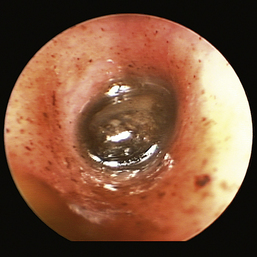

Figure 20-17, p. 596, Ceruminolith in the ear canal of a cat

image

Figure 20-17 Ceruminolith in the horizontal ear canal of a cat.

(Courtesy of Dr. Lynette Cole, The Ohio State University, Columbus, Ohio.)